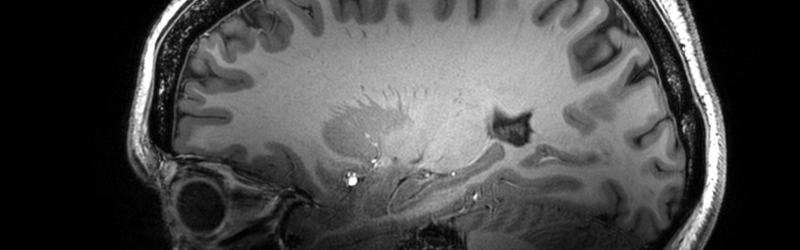

MRI brain scan image

UK’s most powerful MRI scanner

We are establishing the UK’s most powerful MRI scanner as a national facility, which will lead help the UK lead the world in ultra-high field imaging to transform understanding of the brain and treatment of disease.